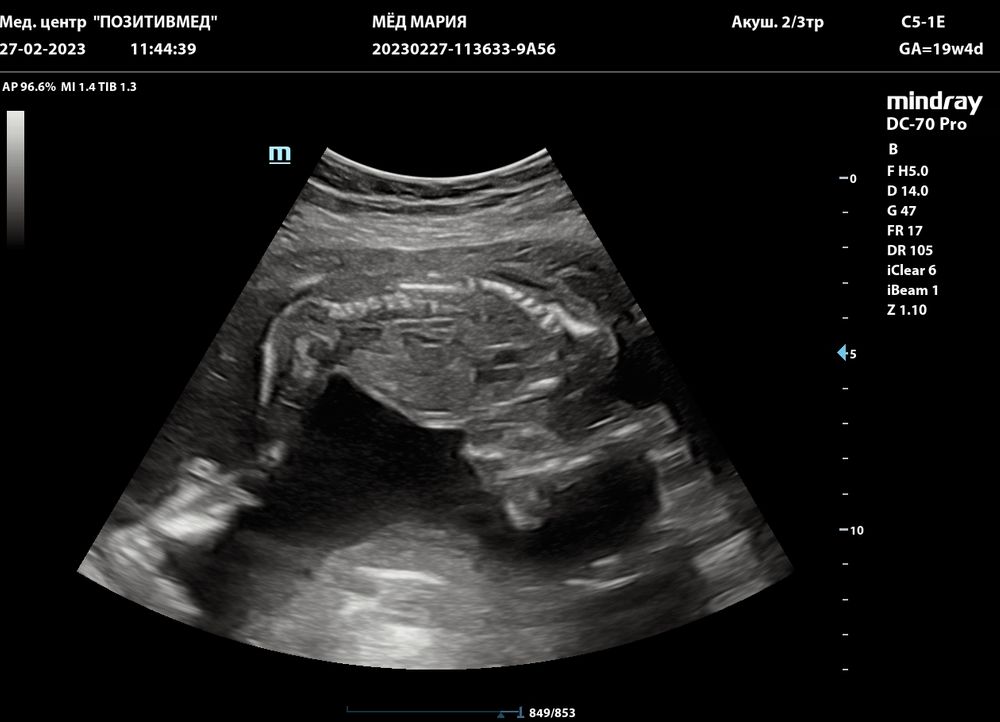

Второй скрининг, наша длинноногая принцесса😌🥰

Ну что, второй скрининг прошёл сегодня успешно - все в норме, даже опережает срок на недельку по данным биометрии (сегодня 19+4, намерили 20+5) Я, как начитавшийся форумчанин, первым делом спросила про носовую косточку - все с ней в порядке) И сердечко 4-х камерное, и все перегородки на месте/симметричные. Лежит, повернувшись вниз лицом, спрашиваю у врача: чего это она так? Развлекается, отвечает, человек, почему бы и нет)))) Ну и фото на память, ноги длинныеееее) Есть в кого - у меня 182 см рост) Булочка наша, мы тебя уже очень сильно любим и ждём!🥰❤️